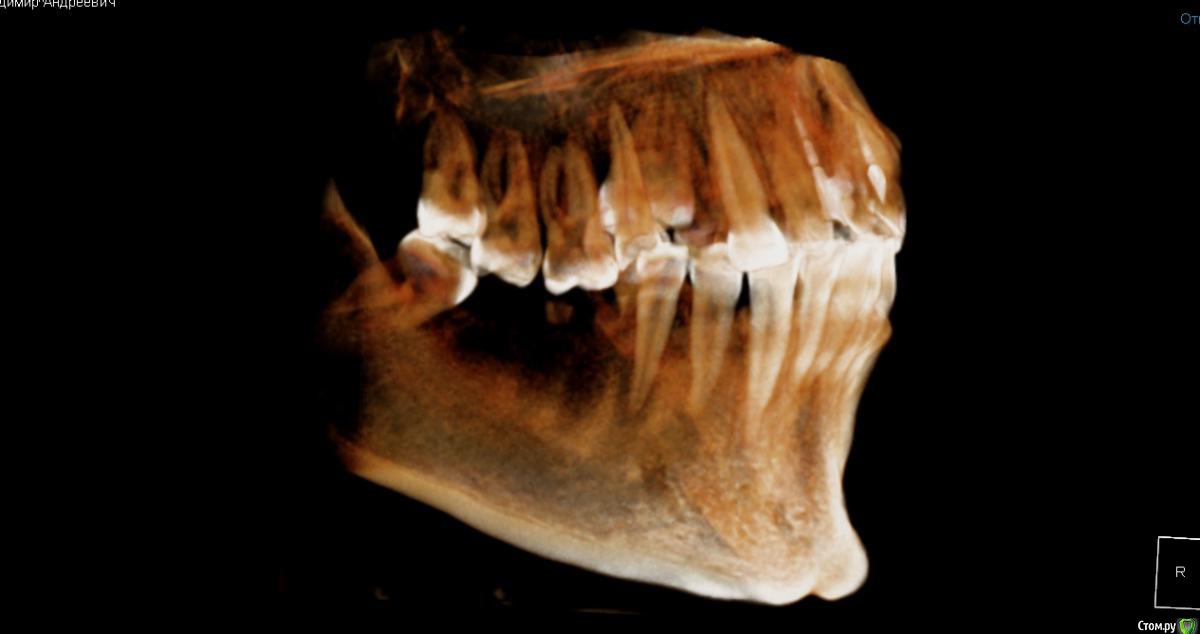

Владимир Андреевич Опубликовано 6 декабря, 2019 Автор Поделиться Опубликовано 6 декабря, 2019 Такой вот еще есть Ссылка на комментарий